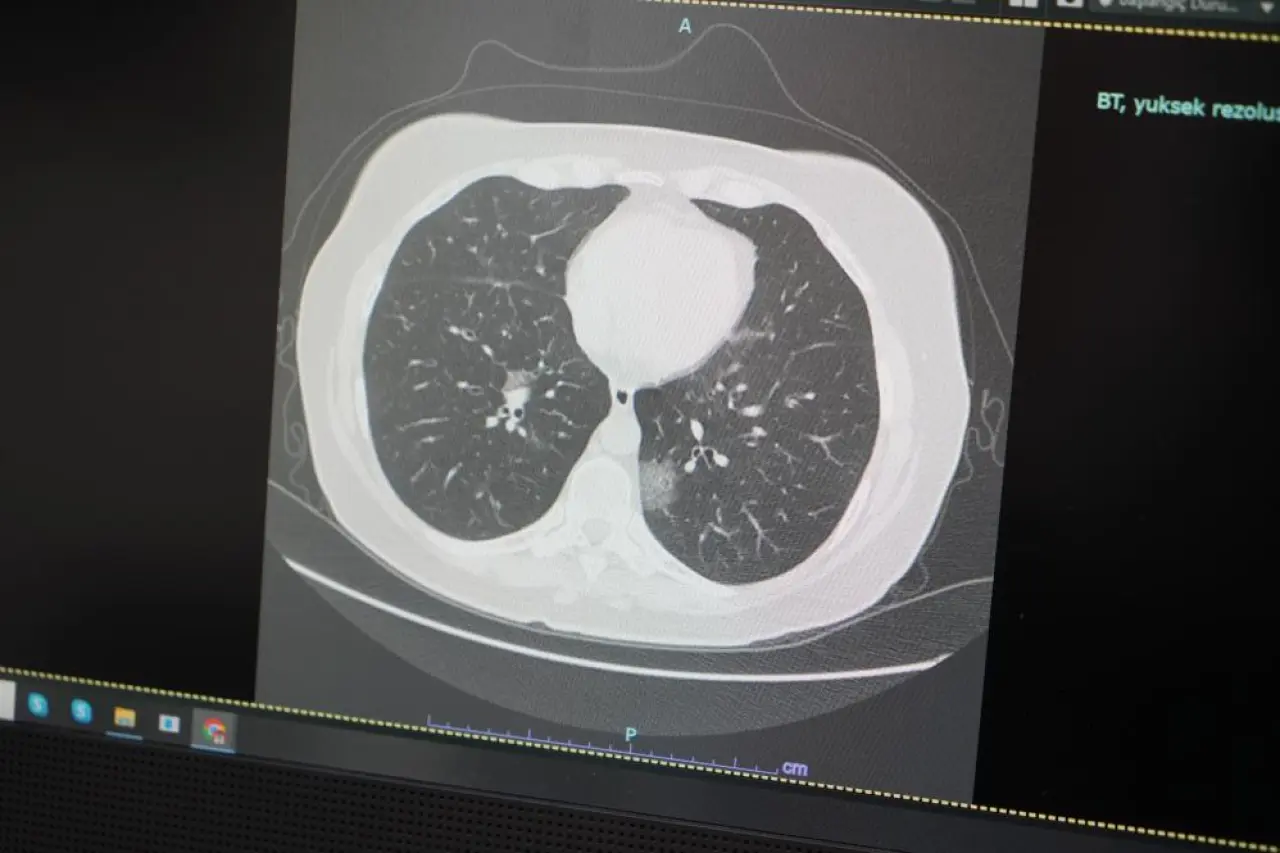

Mayıs ayıyla birlikte doğada yoğunlaşan polenlerin, alerjik bünyeye sahip bireylerde nefes darlığı, öksürük ve burun akıntısı gibi semptomlara yol açabileceğini belirten Özkaya, bu semptomların aynı zamanda Covid-19 ve diğer solunum yolu enfeksiyonlarında da görüldüğünü söyledi. Bu durum, hastaların doğru teşhis almasını güçleştiriyor.

“Hastalıklardaki belirti benzerliği, özellikle uzun süren öksürük, nefes darlığı ve ateş gibi şikâyetlerde halk arasında kafa karışıklığına yol açıyor” diyen Prof. Dr. Özkaya, bu gibi durumlarda mutlaka bir göğüs hastalıkları uzmanına başvurulması gerektiğini vurguladı. Öğretmenlerin ve velilerin bu konuda daha dikkatli olmaları gerektiğini de sözlerine ekledi.